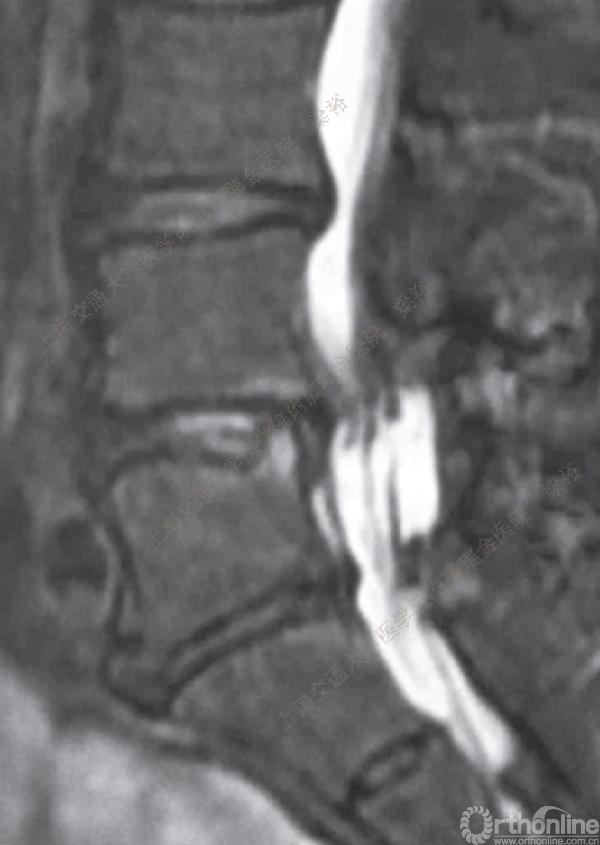

随着微创技术的发展以及手术经验的积累,脊柱微创手术已开始逐步取代传统的脊柱外科手术。微创手术已涉及从颈椎到腰椎的整个脊柱。从简单的椎间盘手术到复杂的 脊椎手术,手术类型越来越多样。在所有的脊柱微创手术中,尤其脊柱内镜手术在过去10年中取得了惊人的进步。在技术发展的同时,脊柱内镜的手术并发症问题也逐渐浮出了水面,针对脊柱内镜手术的并发症与其对策,上海交通大学医学院附属瑞金医院梁裕教授介绍了他们的经验。